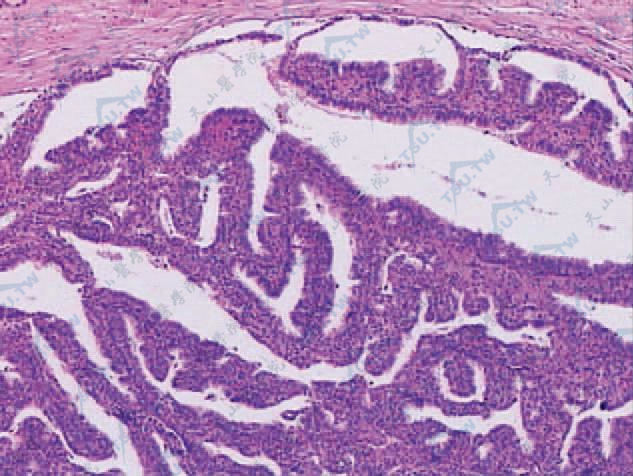

#乳头状汗腺腺瘤

乳头状汗腺腺瘤

临床症状大多数发生在40~50岁女性外阴部,很少发生在20岁以内者。皮损最常见于大阴唇,少数在小阴唇,极少数发生于腋窝、乳房或肛门。肿瘤单发、小而境界清楚、圆形或卵圆形结节状